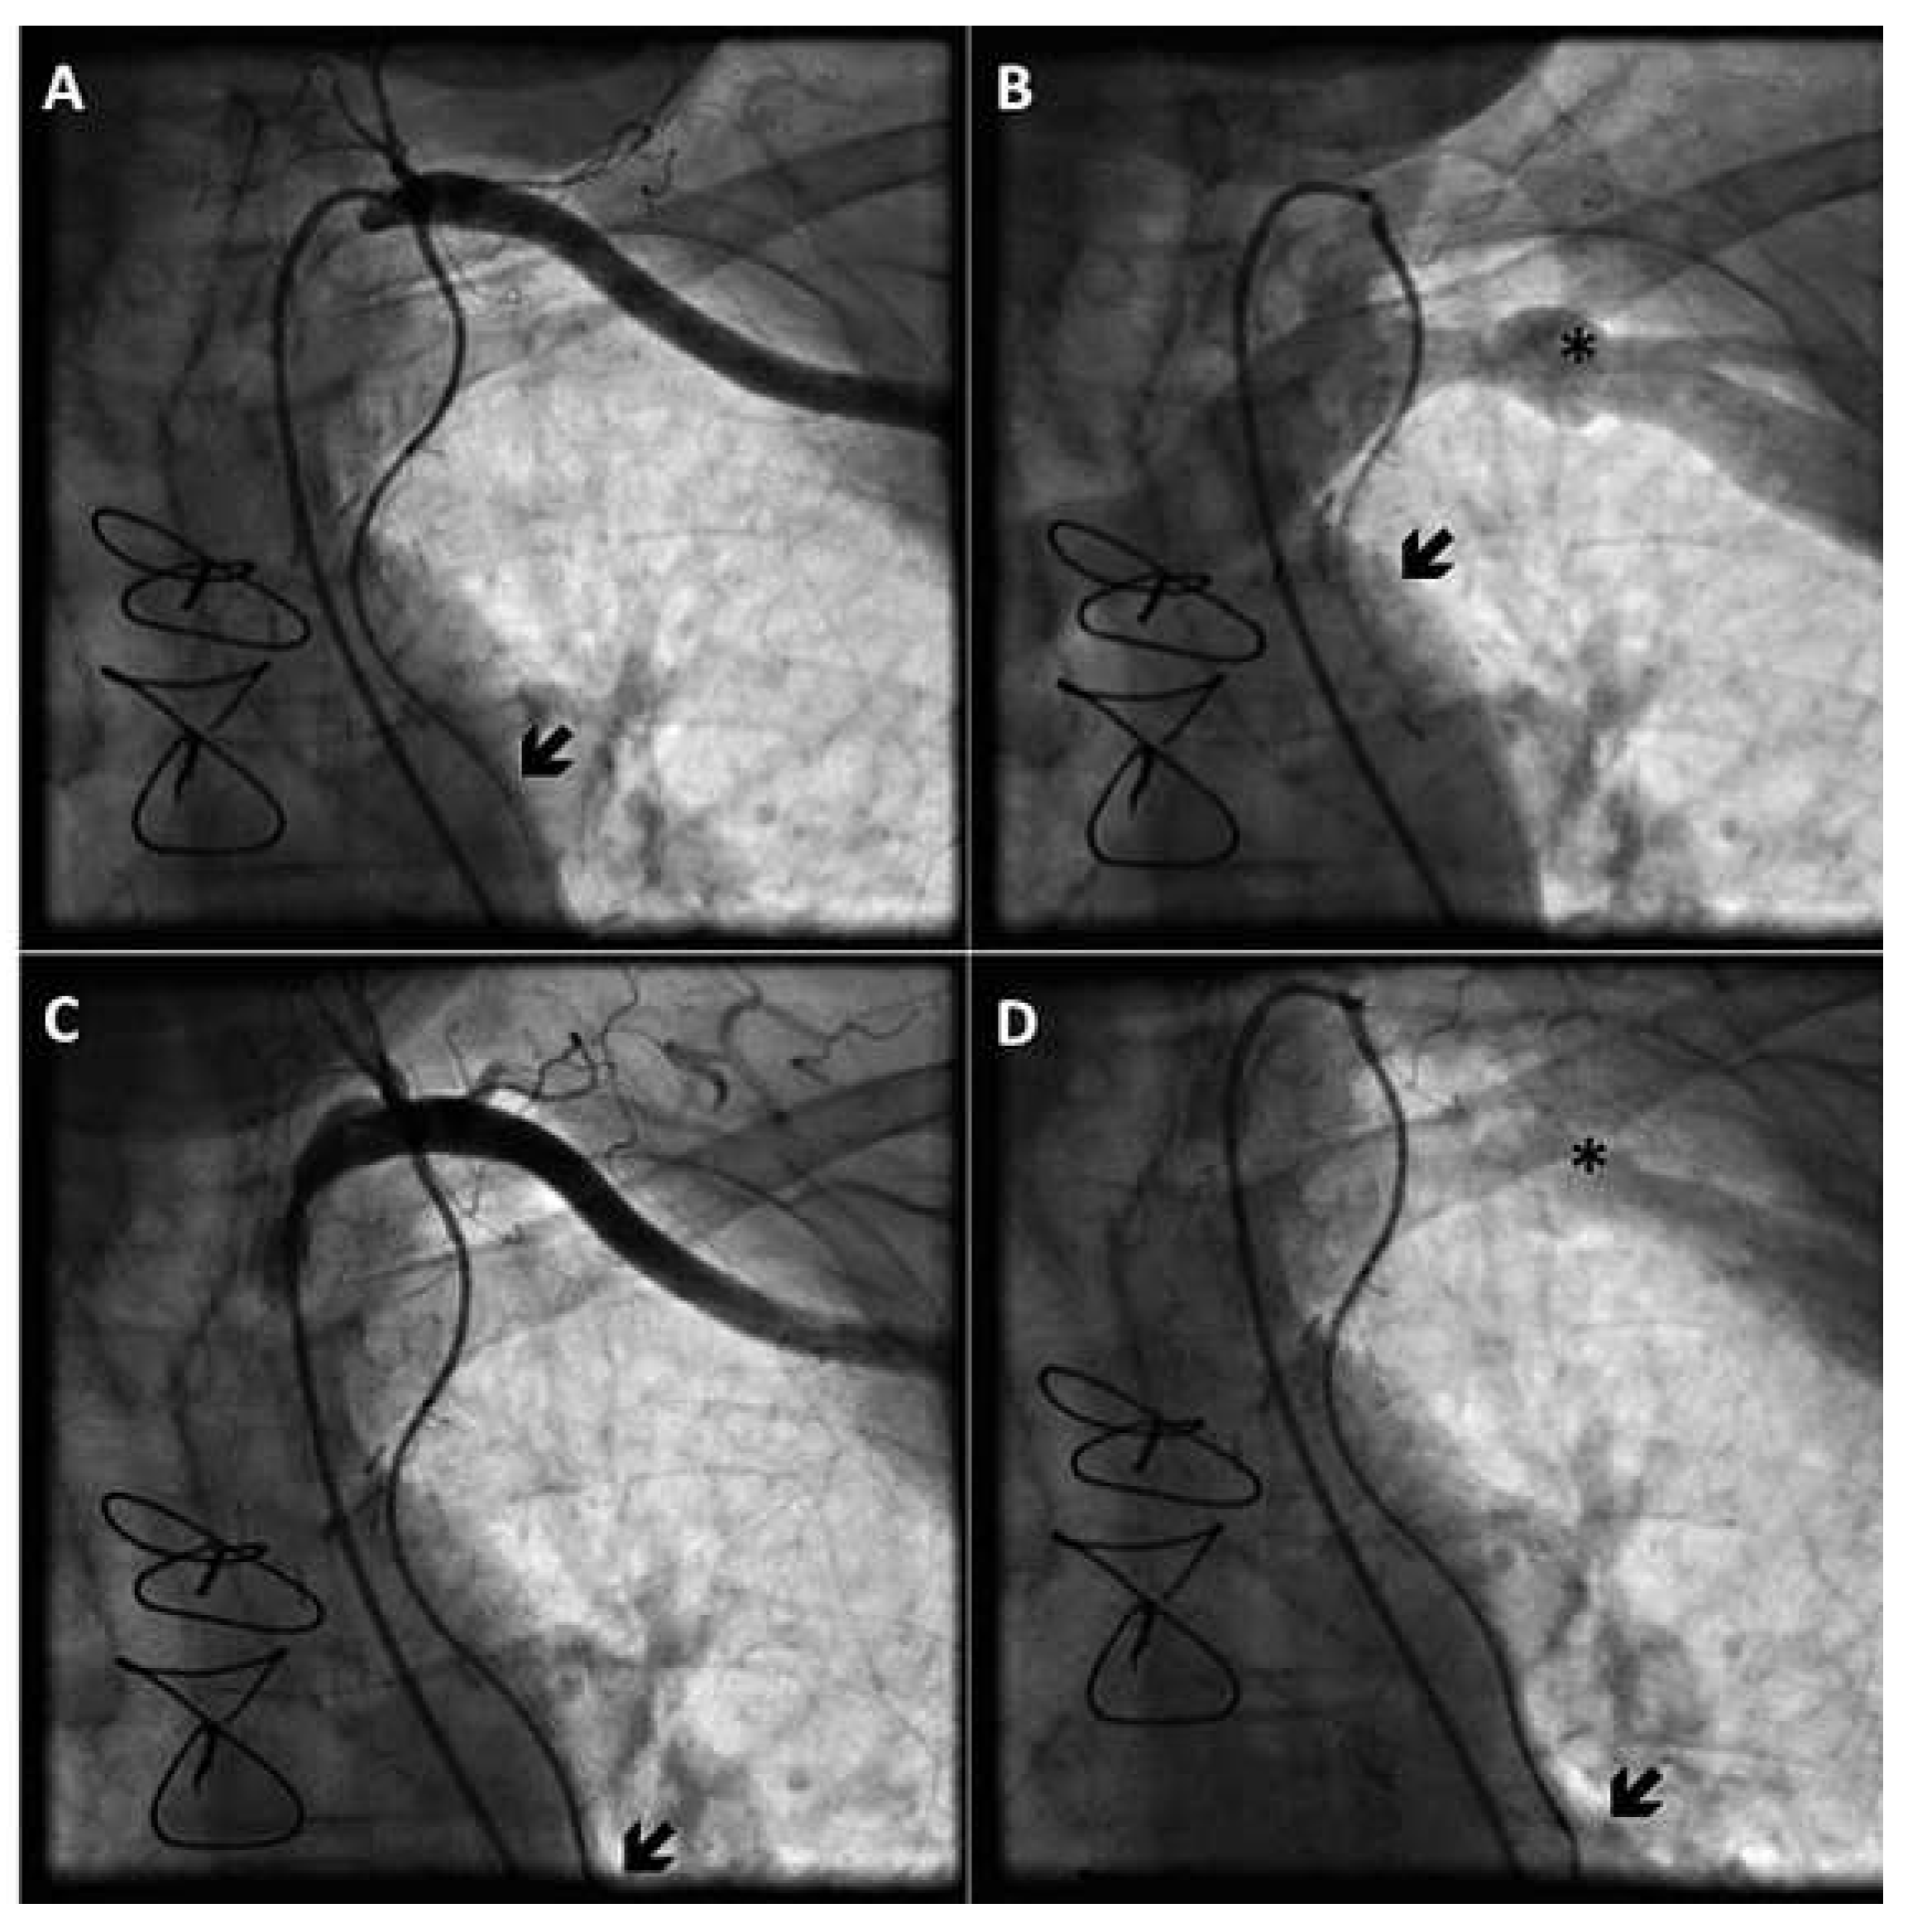

Coronary angiography showed no significant changes compared to the previous exam; all bypass grafts were patent. However, injection of contrast medium into the left main (LM) coronary artery revealed a reverse flow of blood in the left ITA throughout the cardiac cycle, consistent with a coronary steal phenomenon (Figure 1). Even at selective injection into the left ITA, an anomalously competing flow was observed in the bypass graft (Figure 2A,B). Of note, no pressure damping occurred at the intubation of the bypass graft, which rendered the presence of a significant ostial narrowing unlikely.

Figure 1. Reverse flow in the left ITA bypass, visualised at the first selective injection into the LM coronary artery; the black arrow indicates the stenosis (A). Visualisation of the complete left ITA bypass graft from its anastomosis with the mid LAD coronary artery to the left subclavian artery, after selective injection into the LM coronary artery (B).